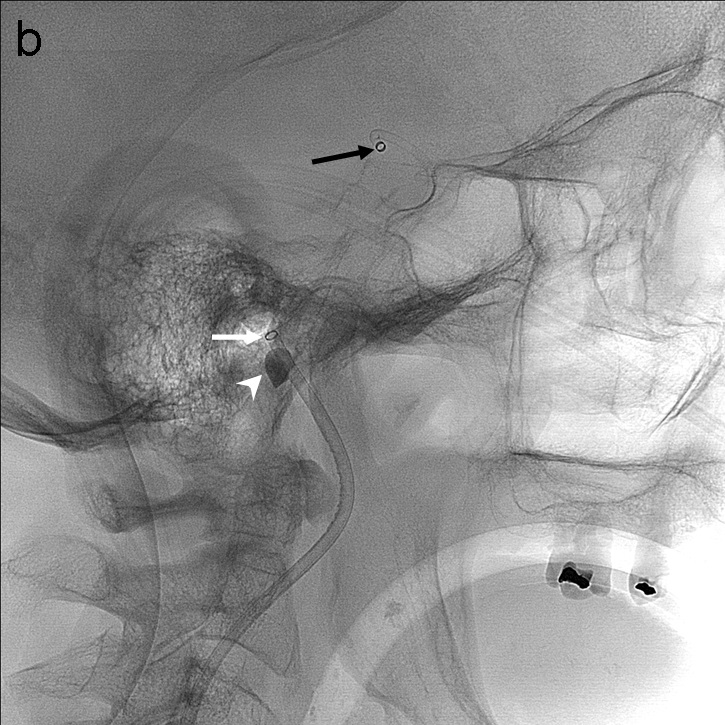

Se realiza una serie a través del catéter balón que demuestra una recanalización parcial del segmento M1 proximal con apertura de arterias lenticuloestriadas y persistencia oclusión de segmento M1 distal de ACM derecha (imagen 3). Se decide cambiar de estrategia y usar la técnica SAVE con Catalyst 5, Trevo Pro 18, Asahi Chikai 0.014’’ y Catch 6 x 30 mm.

La técnica SAVE consiste en combinar stentriever (colocándolo con el trombo en su tercio proximal) y un catéter de aspiración (en contacto con la porción proximal del trombo) y realizar el pase actuando como una unidad, ofreciendo una captura distal (stentreiver) y proximal del coágulo con el catéter de aspiración (imagen 4). Se retiran simultáneamente bajo aspiración con bomba y manual a través del catéter balón.